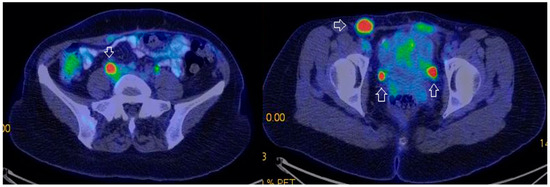

- Tardieu, A.; Ouldamer, L.; Margueritte, F.; Rossard, L.; Lacorre, A.; Bourdel, N.; Lades, G.; Sallée, C.; Monteil, J.; Gauthier, T. Assessment of Lymph Node Involvement with PET-CT in Advanced Epithelial Ovarian Cancer. A FRANCOGYN Group Study. J. Clin. Med. 2021, 10, 602. [Google Scholar] [CrossRef] [PubMed]

- Crestani, A.; Huchon, C.; Mezzadri, M.; Marchand, E.; Place, V.; Cornelis, F.; Touboul, C.; Haddad, B.; Dabi, Y.; Benifla, J.-L.; et al. A Pre-Operative Radiological Score to Predict Lymph Node Metastasis in Advanced Epithelial Ovarian Cancer. J. Gynecol. Obstet. Hum. Reprod. 2022, 51, 102464. [Google Scholar] [CrossRef] [PubMed]